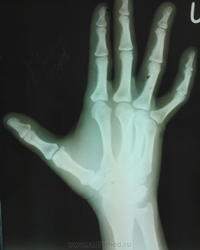

во время стирки одежды игла вонзилась в левую кисть еще весной этого года, с тех пор ее хирурги периодически "наблюдают", один раз амбулаторно пытались извлечь под м\о, не получилось, разок сама съездила в город но там отказали - "такую ерунду могут удалить и ваши хирури", по приезду еще 2 раза в рентген кабинет направляли (наверное подумали что само вышло) и только после этог решили положить в отделение. меня возмутил с каким цинизмом описан анамнез заболевания (фото тоже представлено).  и все это время она ходила страдала с болями в руке, стыдно было смотреть на ее страдальческое лицо сидя в белом халате.

сегодня а описание принесли снимки - инородного тела нет. в истории 2 протокола операции: один - неудачная попытка, во второй раз успех на стороне хирургов (собрались все 3 хирурга на операцию)

я поэтому то и выложил фото из истории болезни, снимки из тех которые были вложены в историю датировались июнем, июлем, и два раза начало сентября. в начале я написал что игла попала весной этого года. поэтому почти год.